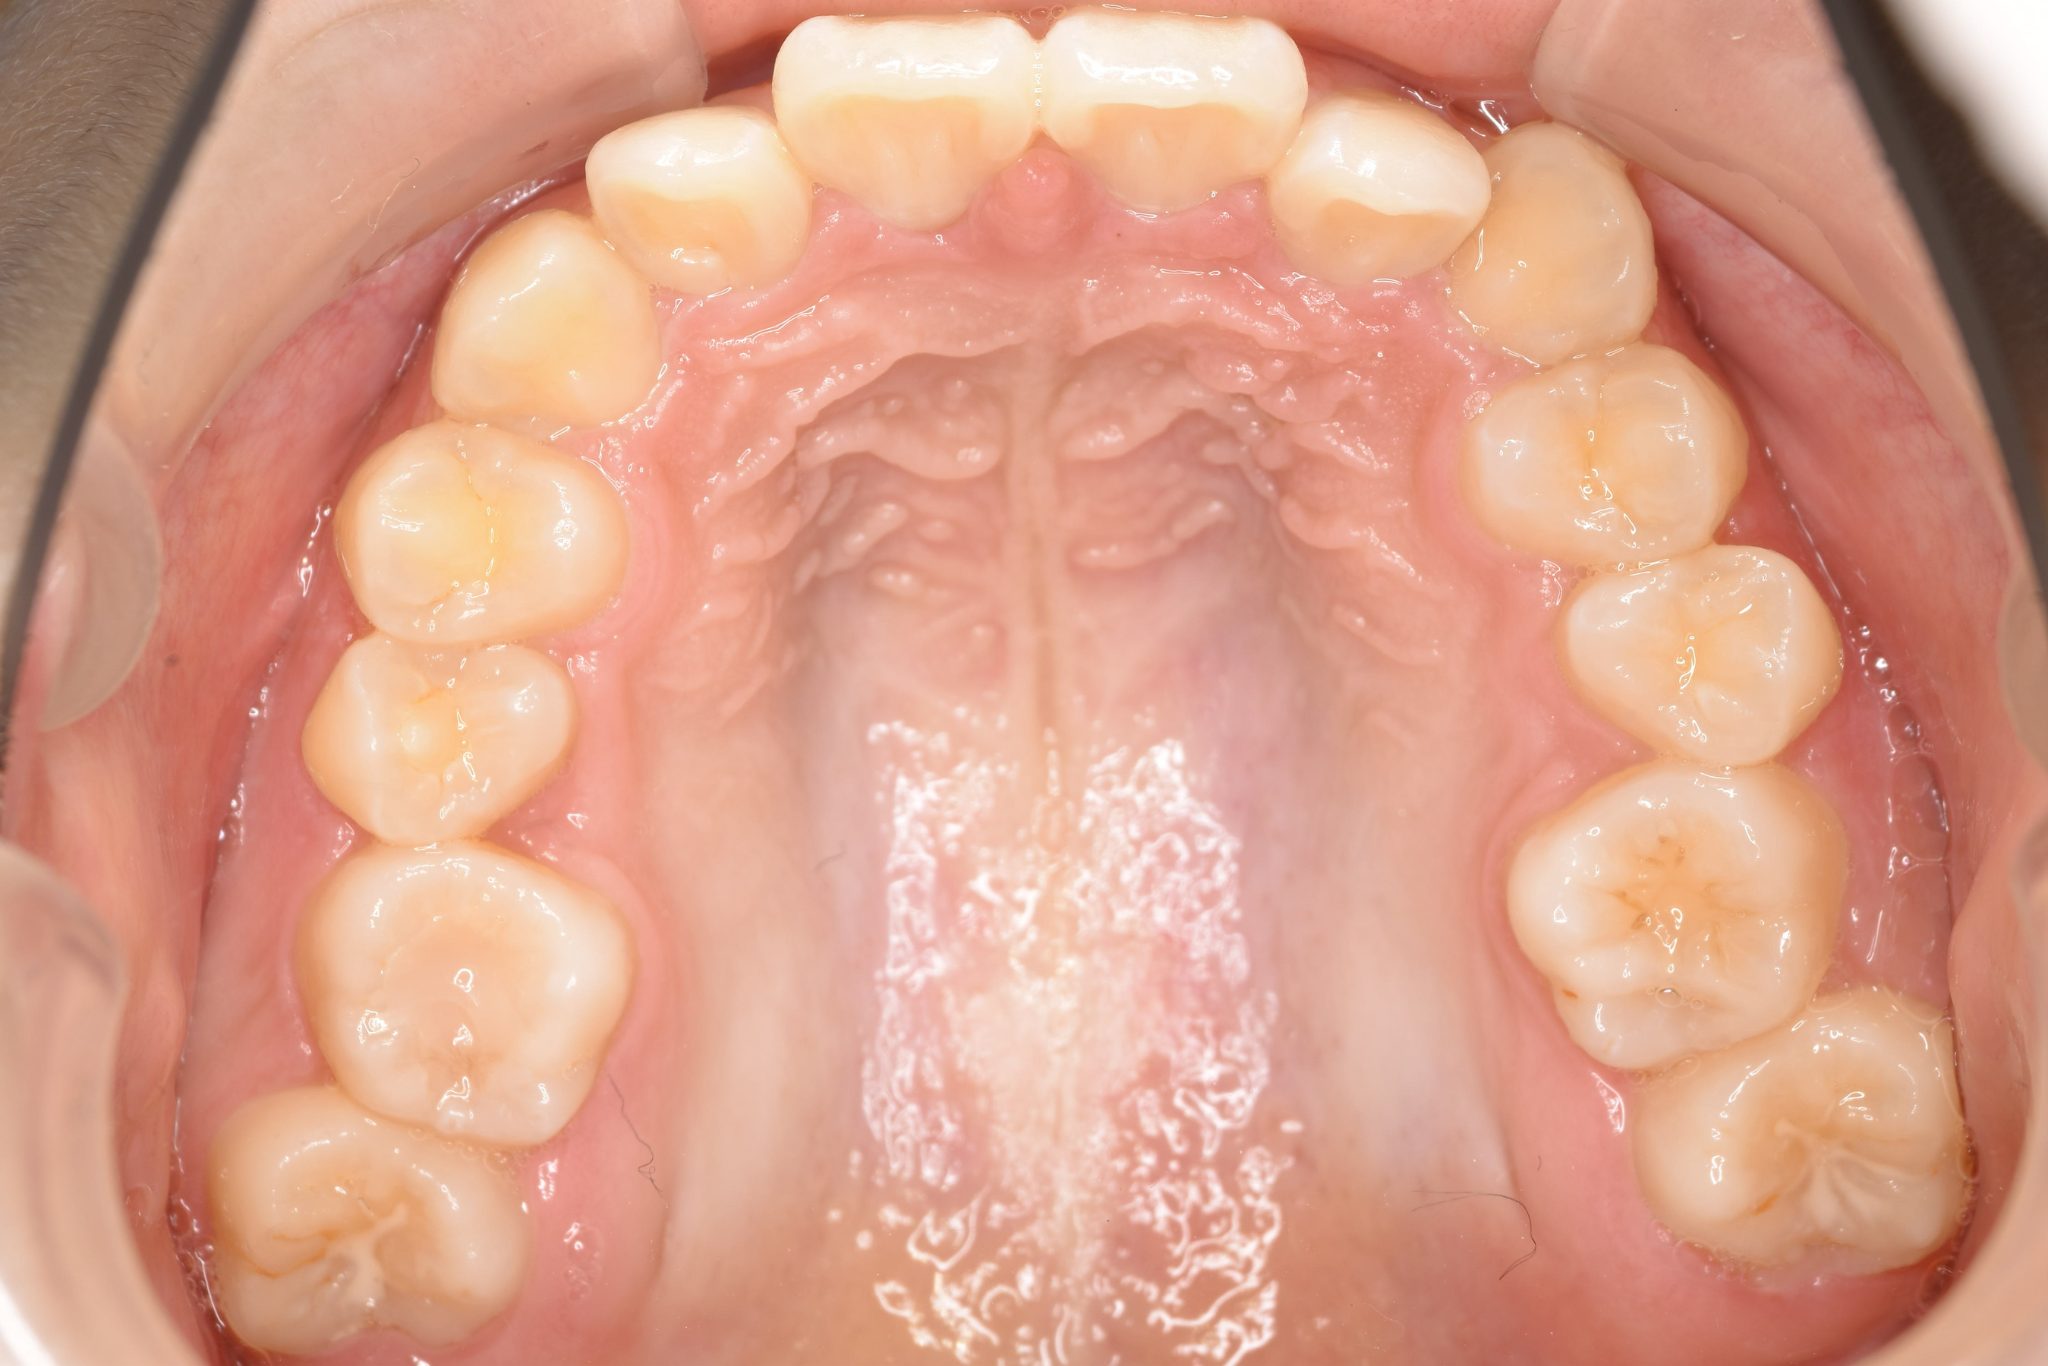

アフター

ワイヤー矯正治療|症例_349

施術内容 MSEと下顎リンガルアーチを用いて上下顎骨を拡大した。

その後マルチブラケット装置を用いて非抜歯で歯牙を配列し、良好な咬合を獲得した。

治癒期間 3年7か月間